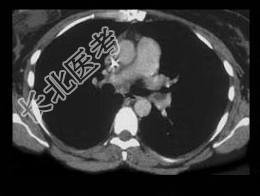

- 单项选择题女,51岁, 心脏手术后,突感胸痛, 结合CT图像,最可能的诊断是 ( )

A、肺栓塞

B、支气管扩张

C、肺水肿

D、肺癌

E、肺不张